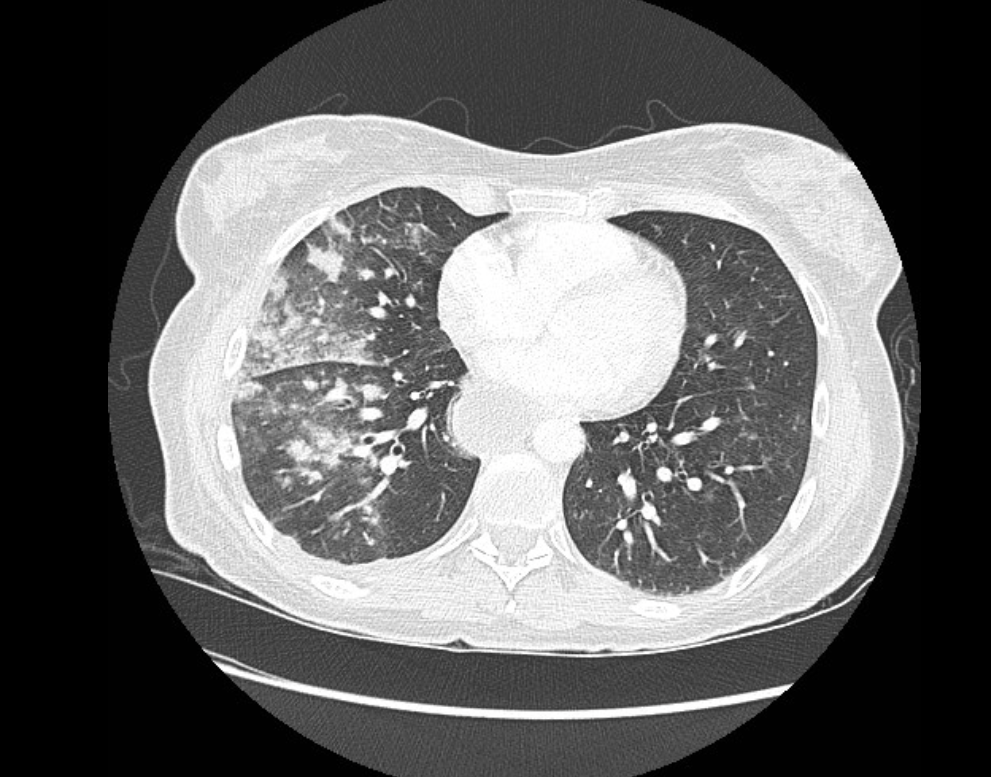

Aspiration pneumonia를 CT에서 감별할 때 가장 중요한 개념은

dependent distribution이다.

이는 중력 방향으로 폐 병변이 분포한다는 의미이다.

흡인된 물질은 기도를 따라 이동하다가

결국 중력 방향으로 내려가게 되기 때문에

폐의 아래쪽이나 뒤쪽 부위에 침윤이 집중되는 경향이 있다.

CT에서 aspiration pneumonia의 전형적인 모습은 patchy consolidation이다.

폐의 특정 폐엽이 완전히 하얗게 차기보다는

불규칙한 음영 증가가 여러 군데 나타나는 경우가 많다.

또한 air bronchogram이 동반될 수 있다.

이는 폐포가 염증성 삼출물로 채워지면서 폐 실질은 하얗게 보이지만

기관지는 여전히 공기를 포함하고 있기 때문에 검은 선 모양으로 보이는 현상이다.

Aspiration pneumonia는 종종 양측 폐에 동시에 나타나기도 한다.

특히 하엽 posterior 부분에서 양측성으로 침윤이 나타나는 경우가 흔하다.

영상에서 aspiration pneumonia를 atelectasis와 구분하는 것은 매우 중요하다.

두 질환 모두 폐의 posterior lower lung에 음영 증가가 나타날 수 있기 때문이다.

그러나 atelectasis에서는

폐 용적 감소(volume loss)가 나타나는 경우가 많고

fissure 이동이나 종격동 이동 같은 소견이 동반될 수 있다.

반면 aspiration pneumonia에서는

폐 용적 감소가 뚜렷하지 않고

폐 실질 내부에 patchy consolidation이 나타나는 경우가 많다.